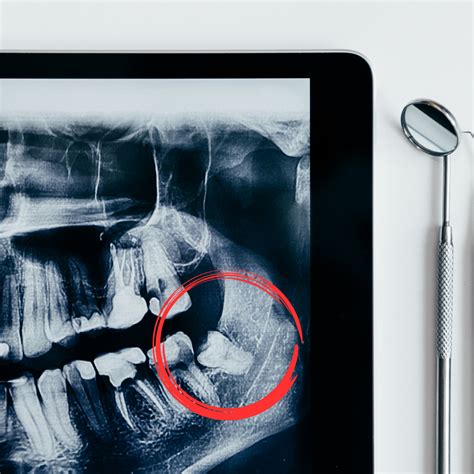

Representación de muelas del juicio impactadas.